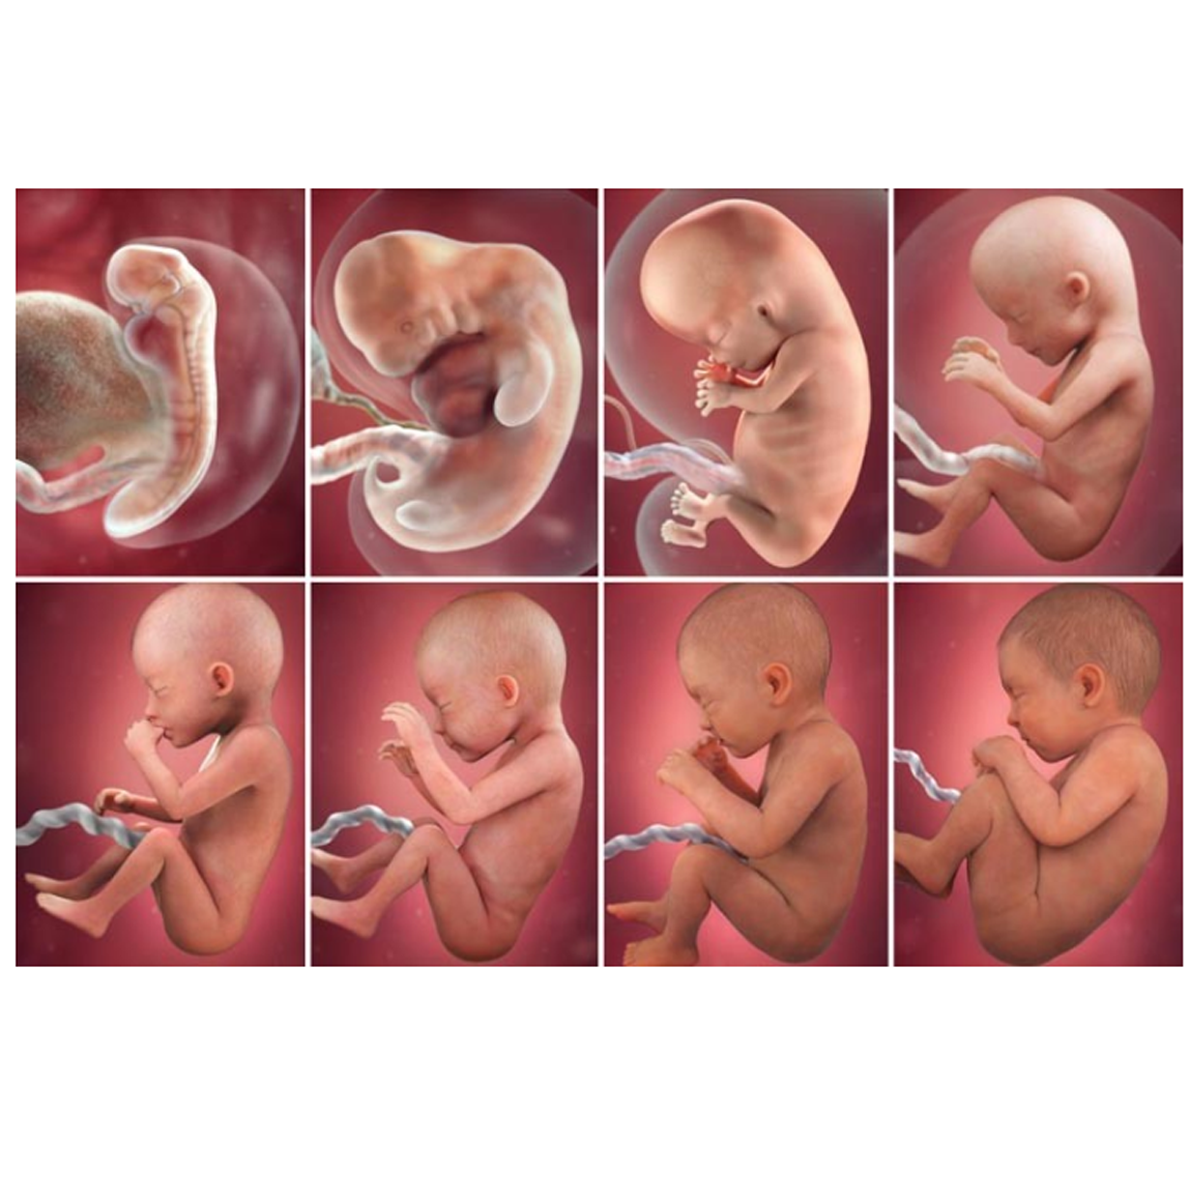

An antenatal ultrasound scan during pregnancy is the first time parents-to-be get to see a baby moving in the womb. High-frequency sound waves, inaudible to the human ear, are transmitted through the abdomen through a device called a transducer to look at the inside of the abdomen.